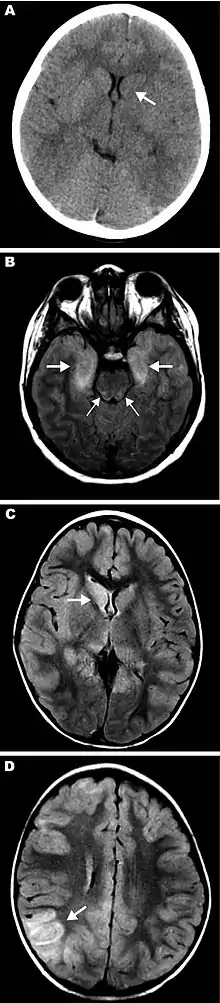

EEE is found today in the eastern part of the United States and is often associated with coastal plains. It can most commonly be found in East Coast and Gulf Coast states.[1] In Florida, about one to two human cases are reported a year, although over 60 cases of equine encephalitis are reported. In years in which conditions are favorable for the disease, the number of equine cases is over 200.[3] Diagnosing equine encephalitis is challenging because many of the symptoms are shared with other illnesses and patients can be asymptomatic. Confirmations may require a sample of cerebral spinal fluid or brain tissue, although CT scans and MRI scans are used to detect encephalitis. This could be an indication that the need to test for EEE is necessary. If a biopsy of the cerebral spinal fluid is taken, it is sent to a specialized laboratory for testing.[4]